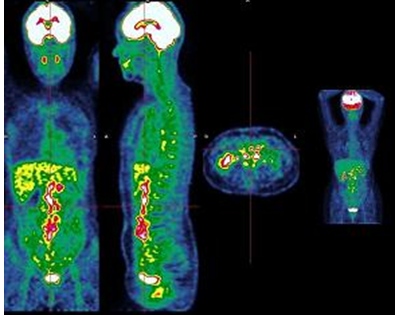

Figure 4 : Image PET avec zones d’hypermétabolisme (colorées) pathologique mais structure anatomique pas clairement affirmée.

Ainsi, la TEP repère les cellules ayant un métabolisme anormal, particulièrement les cellules cancéreuses et le scanner permet de situer les images obtenues à la TEP dans leur environnement anatomique. Il profite donc des fonctions de ces deux formes d'imagerie et les assemble.

Figure 6 : Image PET Scan combinant les avantages des deux technologies.